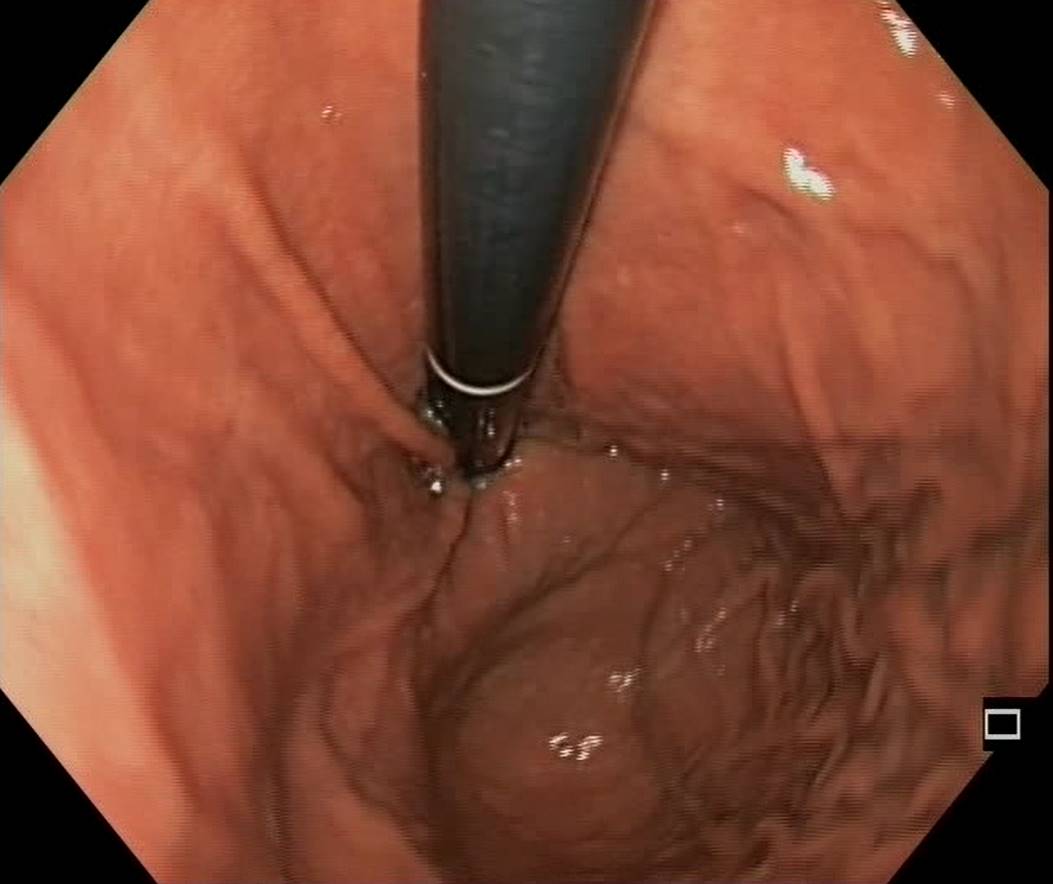

A Normal Gastric Fundus

A normal gastric fundus. Just click on a picture!

Diverticulum in the gastric fundus